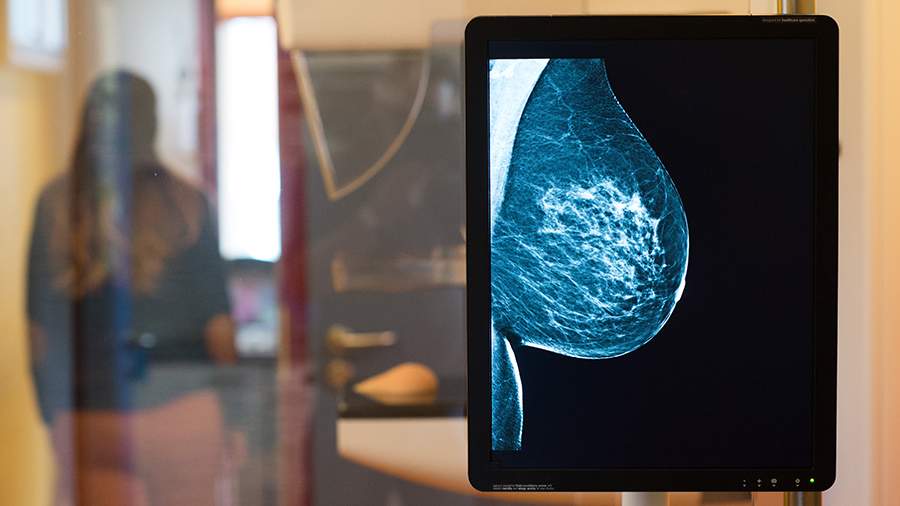

«Самостоятельно осматривать грудь желательно не реже одного раза в месяц. При прощупывании важно обращать внимание на уплотнения в груди и под мышками, изменения формы груди или соска, появление выделений (особенно кровянистых), а также покраснение кожи. При появлении этих признаков необходимо обратиться к гинекологу. Врач проведет осмотр и назначит необходимые исследования. Для регулярного контроля женщинам младше 40 лет рекомендуется ежегодно проходить УЗИ молочных желез, а после 40 — маммографию», — объясняет специалист.